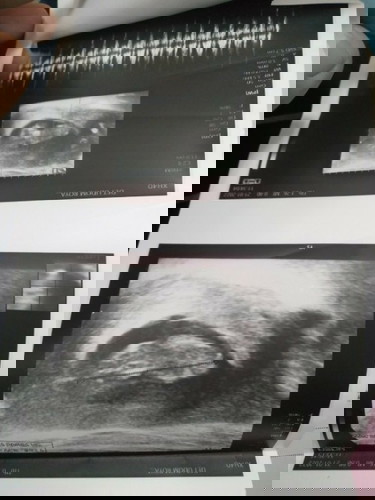

ภาพแรกและสุดท้าย แม่ขอเวลาทำใจ จากการจากไปของน้องอยุ่กับแม่แค่ 12w3d แม่พร้อมแล้วจะกลับมาใหม่นะคะ